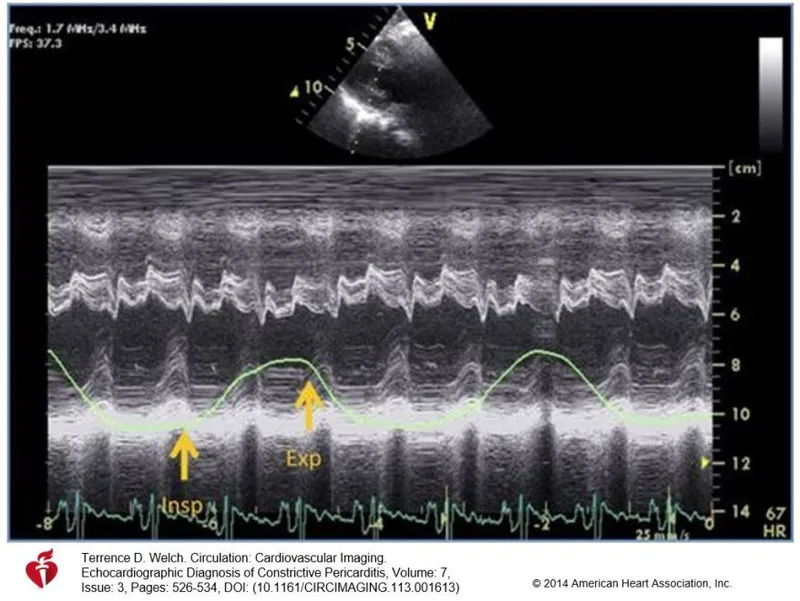

- Echocardiogram: Septal bounce, respiratory interventricular dependence.

- Cardiac Cath: Equalization of diastolic pressures across all chambers; "dip-and-plateau" or square root sign in ventricular pressure tracings.